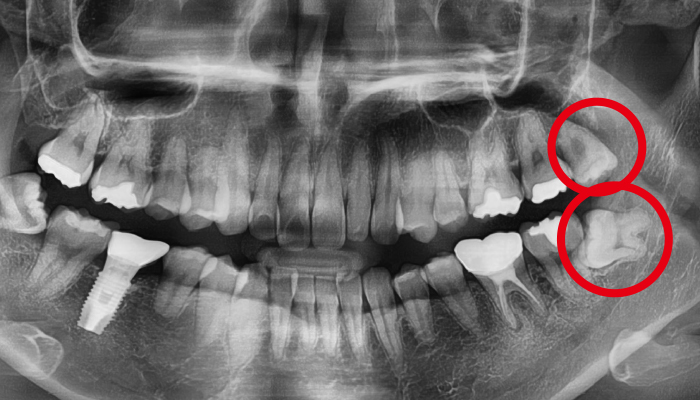

사랑니가 신경과 맞닿아 있는 상황을 제외하고는 안전하고 신속하게 발치가 가능합니다. 사랑니가 비스듬하게 누워있는 경우에는 수술적인 방법을 통해 발치를 해야합니다.

신경과 맞닿아 있는 경우에는 신경손상의 우려가 있음으로 주의하셔야 합니다. 때문에 사랑니 발치는 많은 경험을 가진 의료진에게 받아야 합니다.

사람에 따라 다르지만 사랑니는 대부분 뼈의 자리가 부족하거나 기울어져 나거나 일부분에만 나오게 되어 관리가 매우 힘들고 인접 치아에 충치까지 유발할 수 있습니다. 매복사랑니는 고난이도 기술이기 떄문에 숙련된 의사의 발치가 중요합니다.

어금니 뒤쪽 공간이 부족하여 잇몸을 절개하여 사랑니를 발치하는 과정 중에 치아를 조각내거나 주위의 뼈를 갈아내고 뽑아야 하는 경우도 있습니다

사랑니 발치 전후 사례

• 치료 전

치료 후